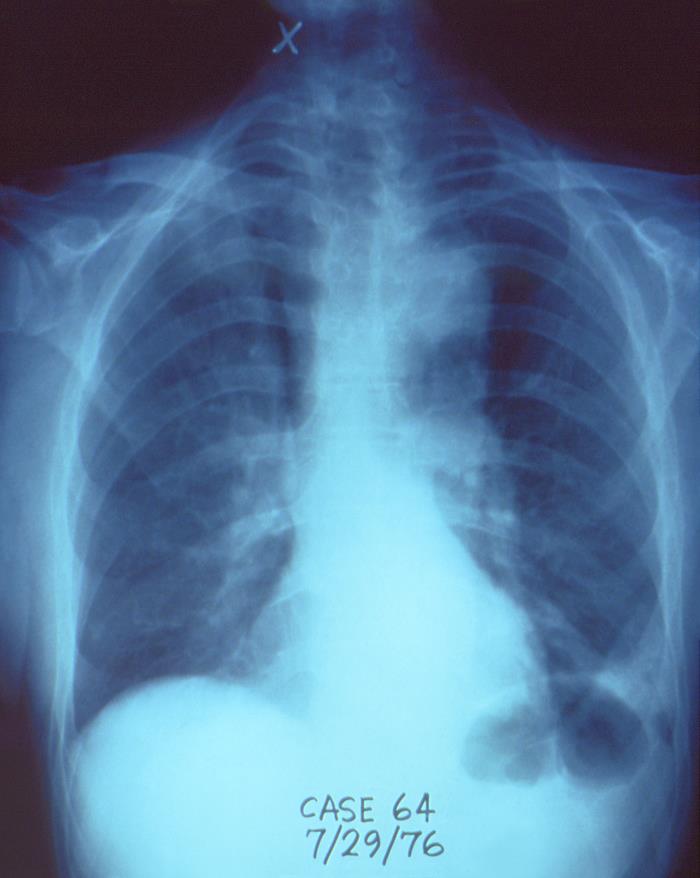

Legionella was discovered after an outbreak in 1976 among people who went to a Philadelphia convention of the American Legion. Those who were affected suffered from a type of pneumonia that eventually became known as Legionnaires’ disease.